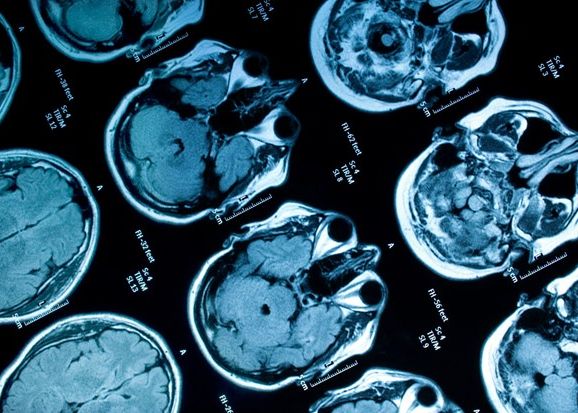

Cercetatorii de la Universitatea Stanford au reusit sa citeasca gandurile unui soarece. Echipa profesorului Mark Schnitzer a implantat in creierul animalului un foarte mic microscop. Folosind pigment fluorescent, ca lumina neuronii care se activau, cercetatorii au reusit sa afle gandurile micutului rozator.

Neuronii au fost implantati intr-o regiune a creierului numita hipocamp, responsabila pentru gandirea spatiala si memoria episodica la soareci, dar si la oameni. Cercetatorii au urmarit activitatea a 700 de neuroni de aici.